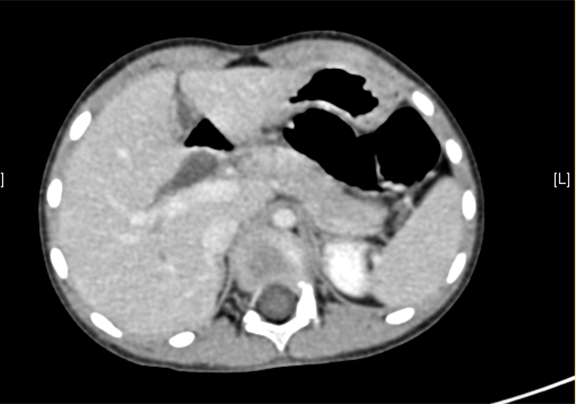

术前CT检查:

平衡期

一般情况:CH-001-CBD-000021,3岁足月产女性患儿,身高105cm,体重16.5kg,

主诉:发现胆总管扩张1月。

现病史:,患儿无明显诱因出现腹痛,无发热不伴有黄疸,在当地医院考虑"胆管扩张症",给予抗炎保守治疗好转。近一个月来患儿未出现腹痛等不良主诉,今日为求进一步诊断来我院,拟诊"先天性胆管囊肿"收入院。

腹部B超:先天性胆总管囊状扩张上腹部CT(外院):胆总管囊肿。